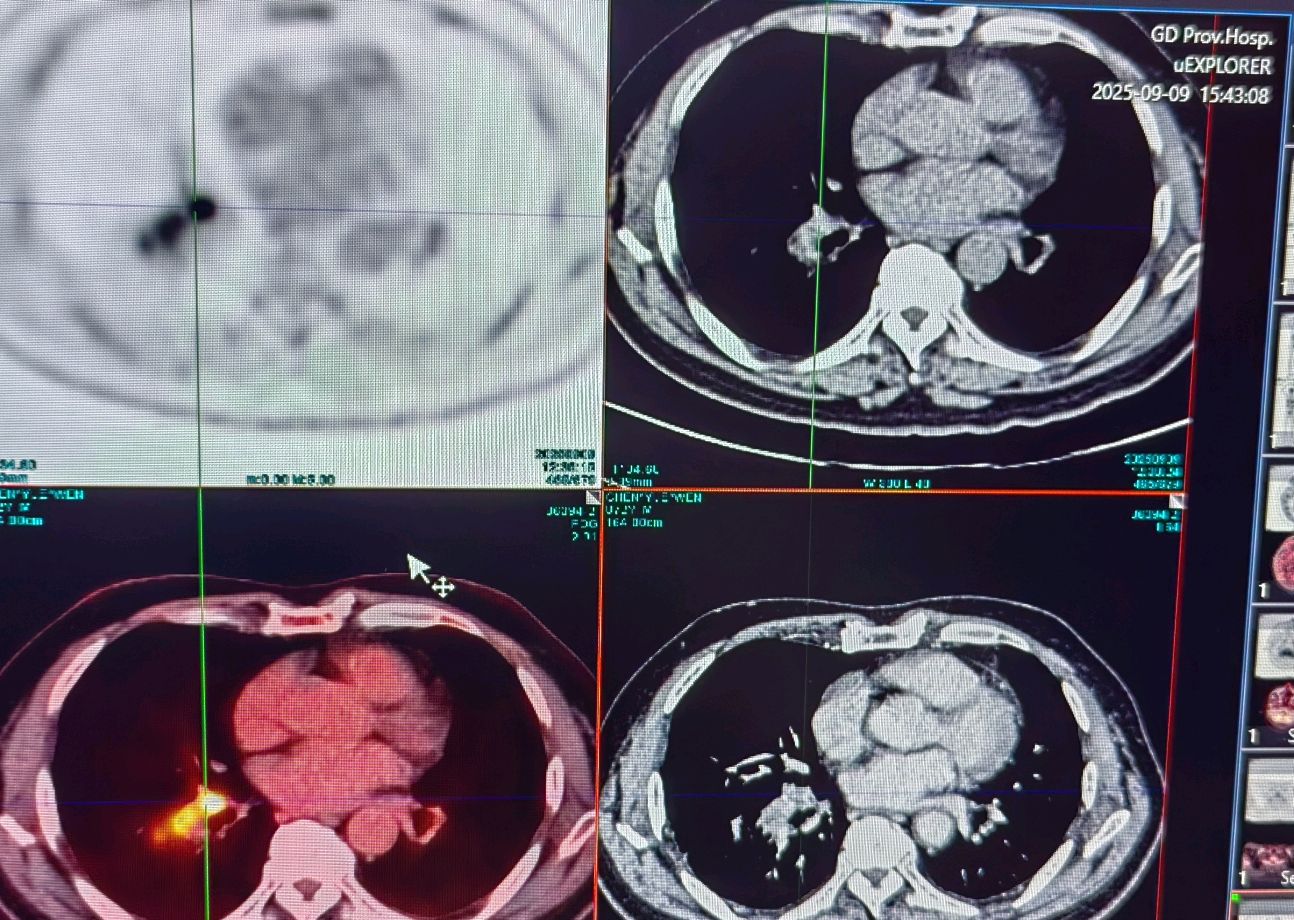

局部晚期肺癌经过化疗联合免疫治疗后一年手术

肺癌 | 免疫治疗联合其他治疗(化疗、放疗、靶向等)!

新辅助治疗后手术切除——中晚期肺癌患者的机遇